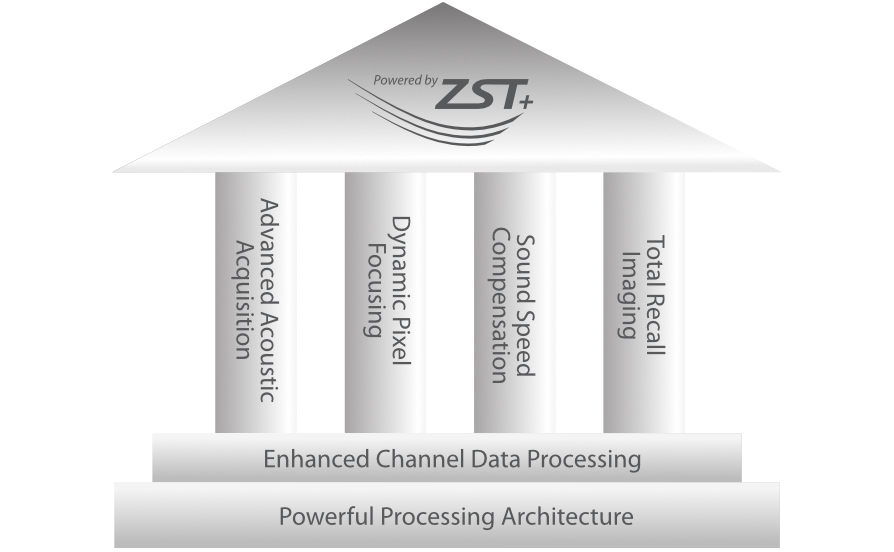

ZST + - nieograniczone mo?liwo?ci obrazowania

Platforma ZST+ to zaawansowane technologiczne narz?dzie, kt├│re zast?puje tradycyjne formowanie wi?zki, przetwarzaniem opartym na danych kana?owych. Dzi?ki temu przezwyci??a ograniczenia zwi?zane z kompromisem pomi?dzy rozdzielczo?ci? przestrzenn?, rozdzielczo?ci? czasow? i jednorodno?ci? tkanki, kt├│re wyst?puj? w tradycyjnych ultrasonografach.